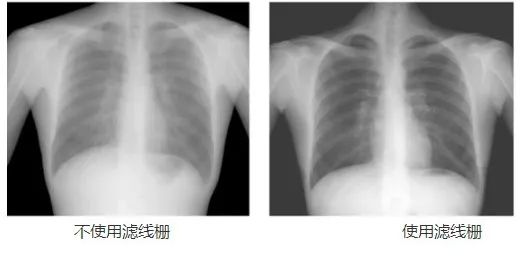

動(dòng)態(tài)DR工作中的常用部件——濾線柵,可以幫助過濾散射線,降低灰霧度,提高對(duì)比度,從而提高成像質(zhì)量